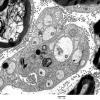

PERIPHERAL NEUROPATHY

4 AXONAL DEGENERATION

3 Electron Microscopy (4)